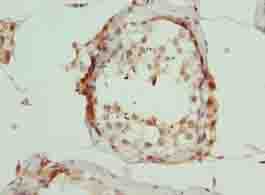

DescriptionARMT1 Polyclonal Antibody. Unconjugated. Raised in: Rabbit.

ApplicationELISA, WB, IHC; Recommended dilution: WB:1:1000-1:5000, IHC:1:20-1:200